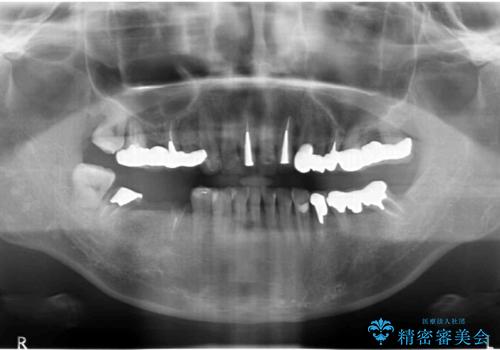

全顎 虫歯 インプラント治療

- 長年悩んでいる歯の見た目や欠損を全て治療したい、と希望され来院されました。

不適合やすり減ったクラウンを全て除去し、虫歯を丁寧に除去したのち精密なセラミック治療を行いました。

また失ってしまった奥歯についてはインプラントを用いて噛み合わせを確立する治療方針としました。

しっかりと調整された咬合関係と、見た目の改善に大変喜んでいただくことができました。